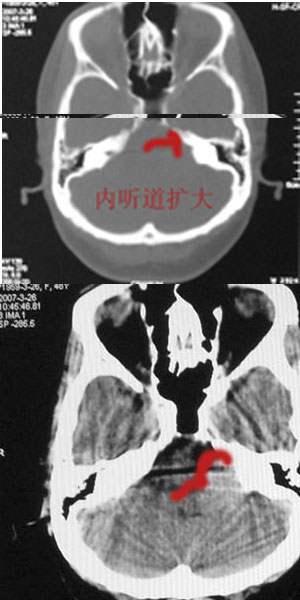

标题: CT8208:女,48岁,反复头晕半年余,无听力、视力障碍 [打印本页]

患者,女,48岁,反复头晕半年余,无听力、视力障碍。病人已手术,结果明天传。

内听道口似未见明显扩大,肿瘤呈类圆形高密度影,考虑脑膜瘤先。

骨窗示内听道未见明显扩大,局部骨质未见明显吸收破坏,

考虑:左侧桥小脑角处脑膜瘤

跨颅窝生长,左侧岩骨“刀切样骨质破坏”高度提示三叉神经瘤!

左侧桥小脑角区高密度肿块,周围无水肿及明显占位效应,岩骨尖受压吸收,内听道未见扩大,无听力异常,右侧颅骨外板高密度影,边缘锐利,考虑:左侧脑膜瘤,右侧颅骨骨瘤。左侧岩骨尖有破坏,三叉神经瘤待排。

结果:脑膜瘤,谢谢。